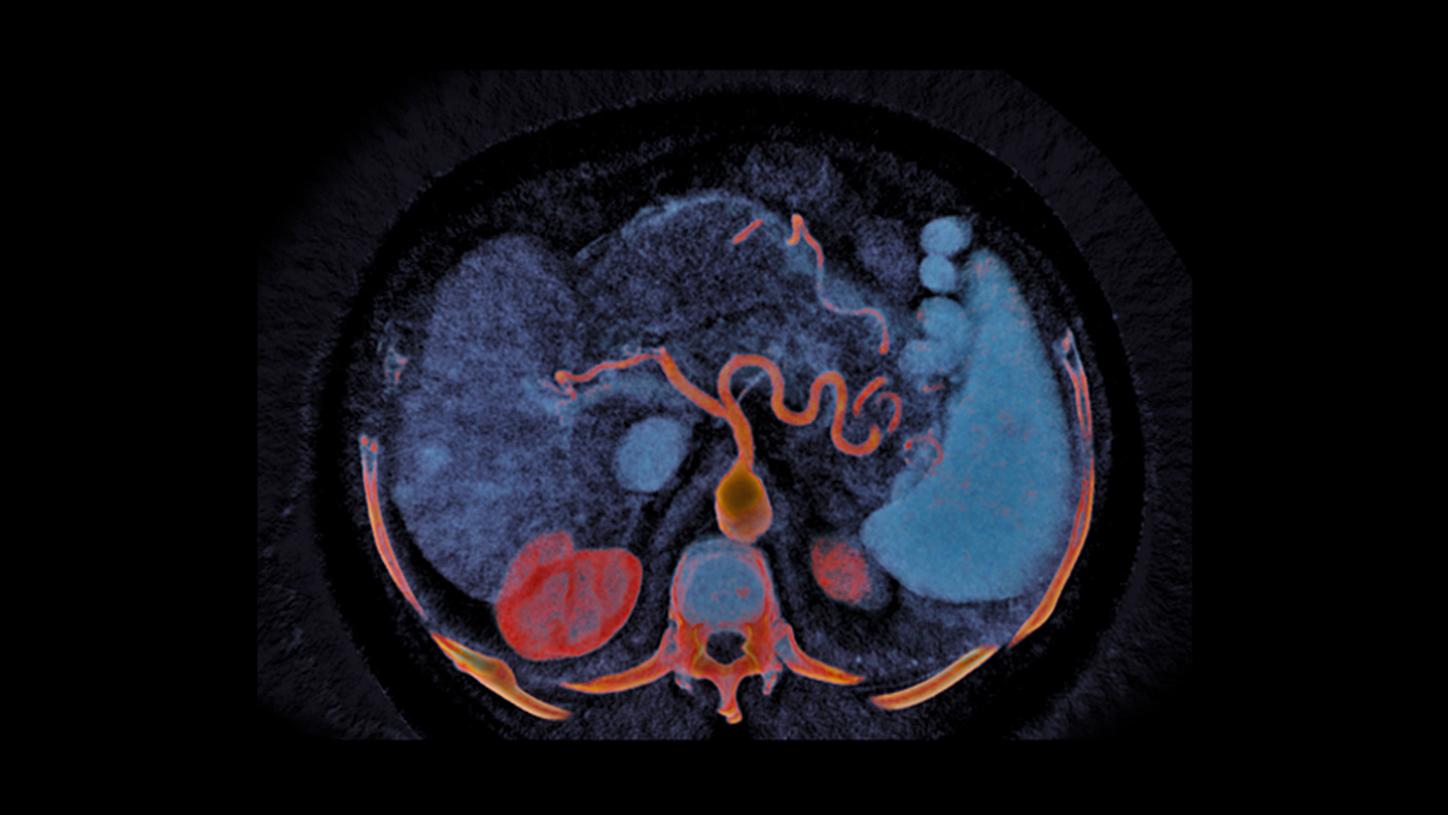

At the heart of NAEOTOM Alpha® is a radically new photon-counting detector. The QuantaMax detector directly converts X-rays into an electrical signal, which is then used to create an image. The energy of each X-ray is measured, so spectral information is available for every scan, and the images are contrast-rich with high spatial resolution at the same dose. Combining the high spatial resolution of the QuantaMax photon-counting detector with our Dual Source temporal resolution enables the visualization of fine details for increased diagnostic confidence.